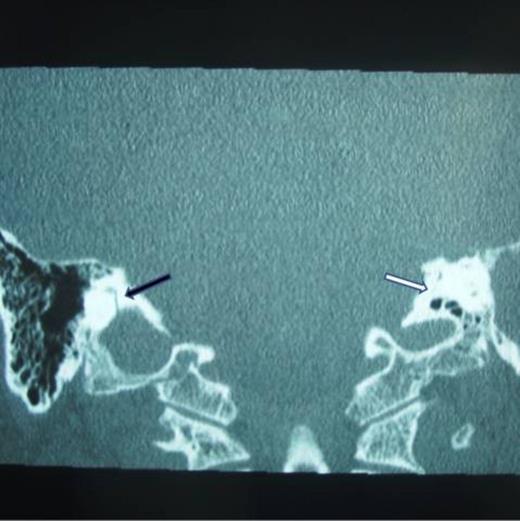

When surgery was attempted, cochleostomy revealed complete obliteration of the scala tympani. Efforts to insert the electrode through the scala vestibuli were also unsuccessful. The procedure was abandoned and a subsequent high resolution CT scan showed complete ossification of the left cochlea and but a patent cochlea on the right (Fig. 3 and 4). Twenty days following the initial attempt, a right cochlear implantation was successfully performed. Following mapping, programming, and aural rehabilitation, the patient was able to understand speech and use the telephone.